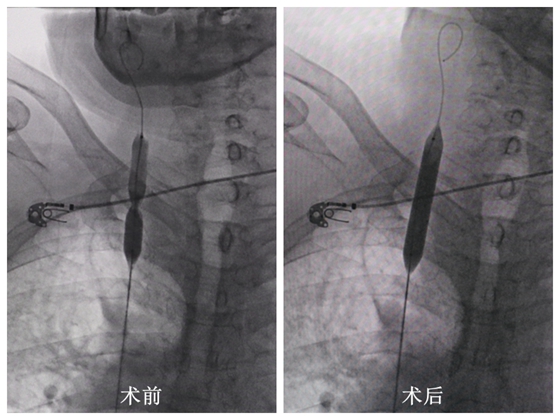

术后,患者血管狭窄处顺利扩张,静脉置入长期管

成小苗主任立即求助于放射介入科主任胡康新教授,也是昔日共事于湘雅医院的同仁。10月12日,胡康新教授带领的汤金城主治医师,李毅副主任医师介入团队给患者造影证实:左侧颈内静脉严重扭曲,右颈内静脉与右锁骨下静脉汇合处暨“头臂静脉起始段”严重狭窄。介入团队立即决定给雷大爷行头臂静脉狭窄球囊扩张术,在血管顺利扩张后,肾内科团队接力,由党智杰主治医师立即为患者放置长期静脉置管。手术过程顺利,雷大爷终于做上了透析,家属和医生的心都落地了。